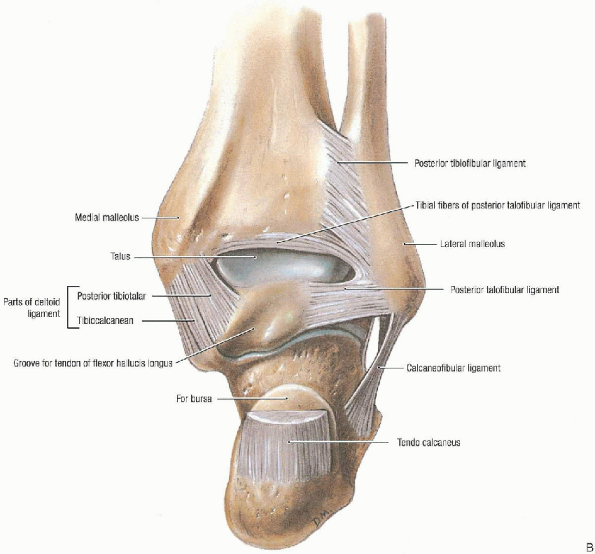

FIGURE 32-1. Ankle joint: anterior view (A) and posterior view (B). (From Agur AMR, Lee MJ. Grant’s atlas of anatomy, 10th ed. Philadelphia: Lippincott Williams & Wilkins, 1999, with permission.)

ankle joint (tibiotalar) includes the distal tibia and fibula and the

talar body (Fig. 32-1). As the tibial shaft

flares in the supramalleolar region, the dense cortical bone changes to

metaphyseal cancellous bone. The shape of the tibial articular surface

is concave with distal extension of the anterior and posterior lips.

This surface has been called the tibial plafond, which is a French word meaning ceiling.

The wedge-shaped talar dome sits within the mortise and is wider

anteriorly than posteriorly. When the ankle dorsiflexes, there is a

compensatory external rotation of the fibula. This leads to abduction

of the foot. The malleoli serve as pulleys for tendons reaching plantar

surface of the foot from the posterior and lateral compartments of the

leg.

posteriorly and is reinforced by collateral ligaments medially and

laterally. On the medial side, the heavy deltoid ligament is attached

above to the medial malleolus with its superficial fibers from the

anterior colliculus and stronger deep fibers originating from the

posterior colliculus. These fibers fan out to attach inferiorly to the

talus and calcaneus. The anterior talofibular, calcaneofibular, and

posterior talofibular ligaments are attached to the lateral malleolus.

The syndesmotic ligament complex includes the anteroinferior and

posteroinferior tibial-fibular ligaments, the interosseous ligament,

and the transverse tibial-fibular ligament and functions to stabilize

the distal fibula with the distal tibia.